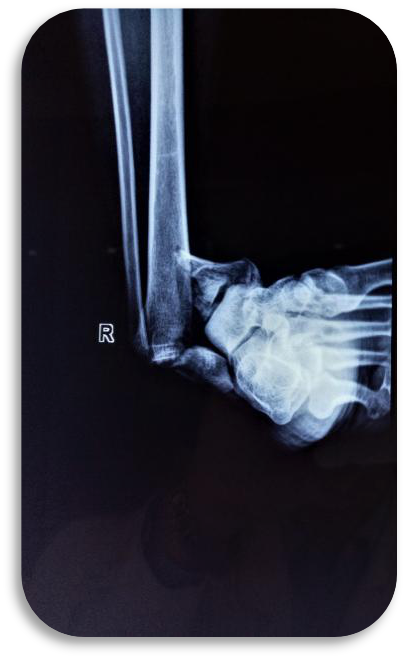

桡骨远端骨折Case1

桡骨远端骨折Case 2

桡骨远端骨折Case3

桡骨远端骨折Case4

桡骨远端骨折Case5

骨远端骨折Case6

桡骨远端骨折Case7